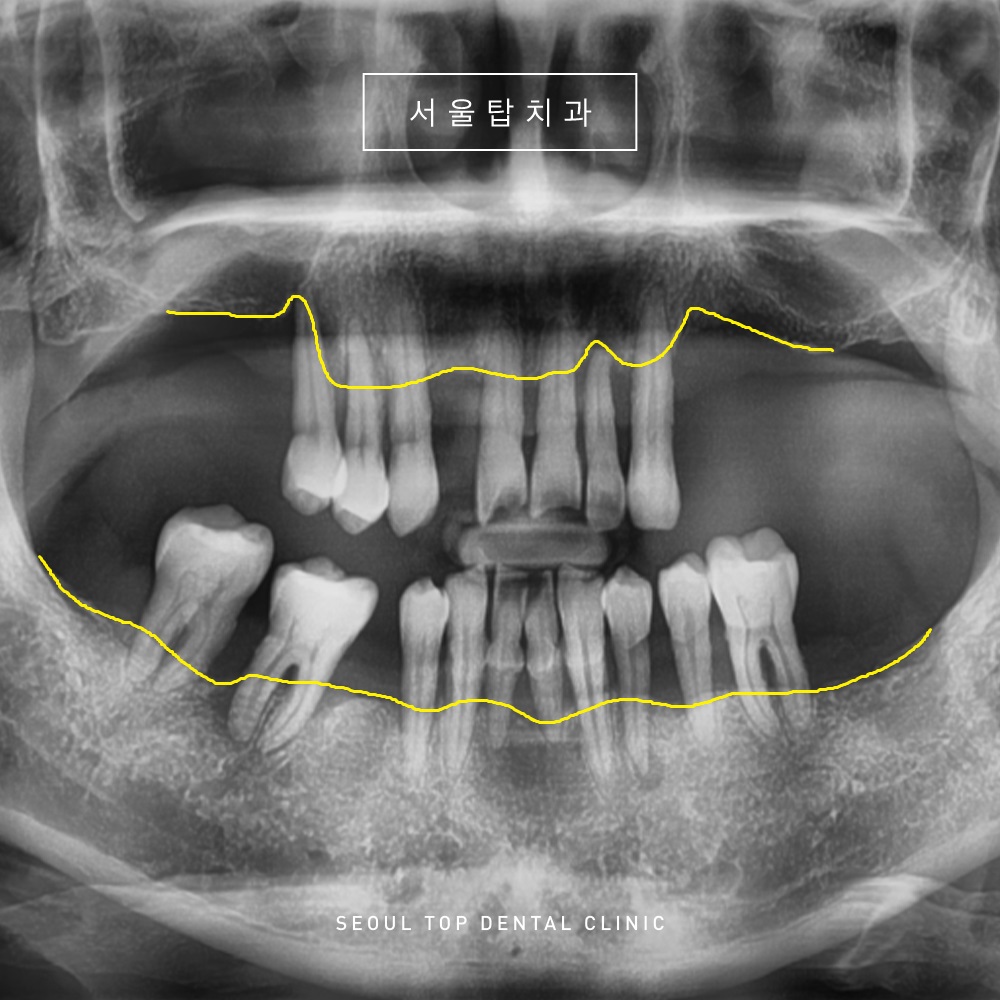

위의 환자분께서는

저작에 불편함을 느껴

치과에 내원을 해주셨는데요.

전반적으로 치아 상실과 더불어

잇몸뼈도 많이 녹아

남아있는 치아들도

많이 흔들리는 상태였습니다.

노란색 표시의 선을 보시면

잇몸뼈가 치아 뿌리에만 걸쳐져 있어

뿌리만 대롱대롱

달려 있는 상황입니다.

물론 가능하다면

치아들을 살려 사용할 수 있으면 좋겠지만,

해당 치아들은

도저히 살릴 수 없는 상황이었습니다.